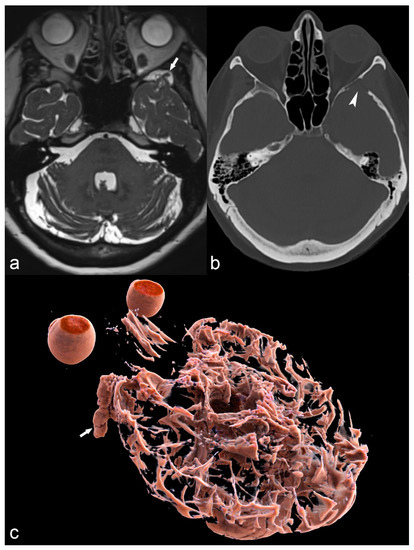

Meningoencephaloceles are probably an underreported cause of epilepsy, most commonly located in the middle cranial fossa. Smaller or larger bony defects of the greater wing of the sphenoid can result in encephaloceles, which cause irritation of the cortex and epilepsy, and their depiction sometimes requires a combination of thin-slice CT in the bony window and high-resolution coronal T2 MRI images (Figure 14).

Figure 14.

68-year-old woman with left temporal meningoencephalocele. Axial 3D high-ponderated T2 sequence (a) shows herniation of abnormal brain parenchyma, meninges and cerebrospinal fluid (arrow) into a defect of the greater wing of the sphenoid bone, best seen on CT in the bone window (arrowhead in (b)). This is further illustrated by a 3D cinematic rendering of the 3D T2 acquisition with a left posterior-anterior oblique vantage point (c), which demonstrates the full caudal extent of the meningoencephalocele within the sphenoid bone (arrow).